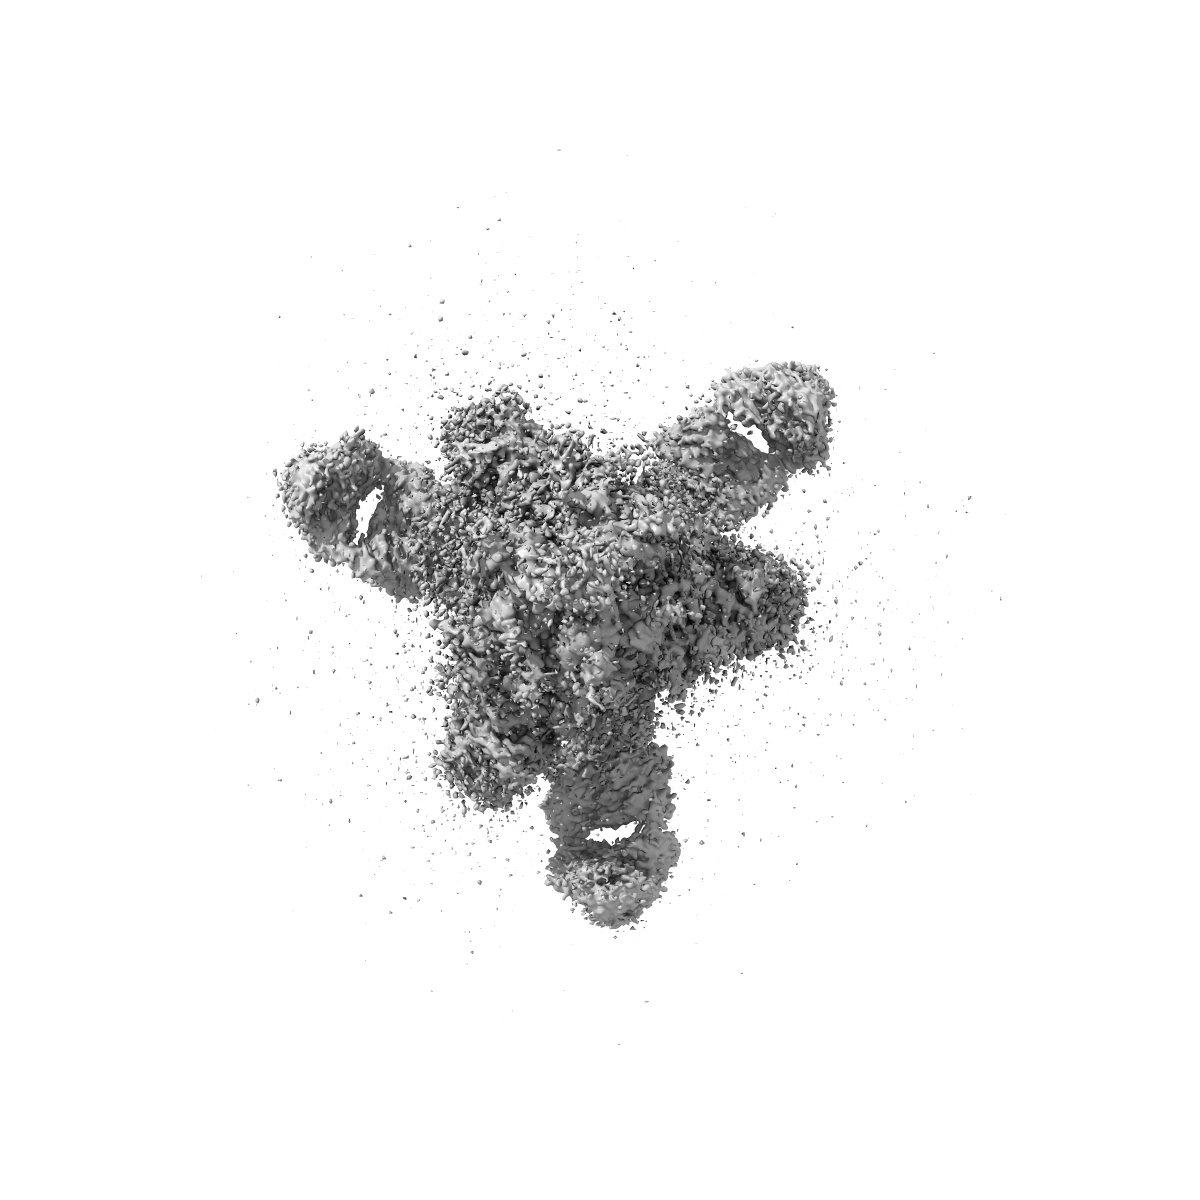

Cryo-EM structure of SARS-CoV-2 Delta Spike protein in complex with BA7054 and BA7125 fab

Single-particle3.2 Å

Sample: Cryo-EM structure of SARS-CoV-2 Delta Spike protein in complex with BA7054 and BA7125 fab